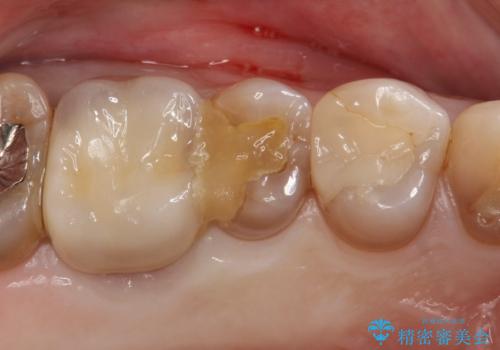

[ 歯周外科 ] 縁下マージン・縁下カリエスの治療

![[ 歯周外科 ] 縁下マージン・縁下カリエスの治療の症例 治療前](https://seimitsushinbi.jp/wp/wp-content/uploads/2022/04/b464b4c5c3053a5fc84212fb664a039f-500x350.jpg?v=1648866777)